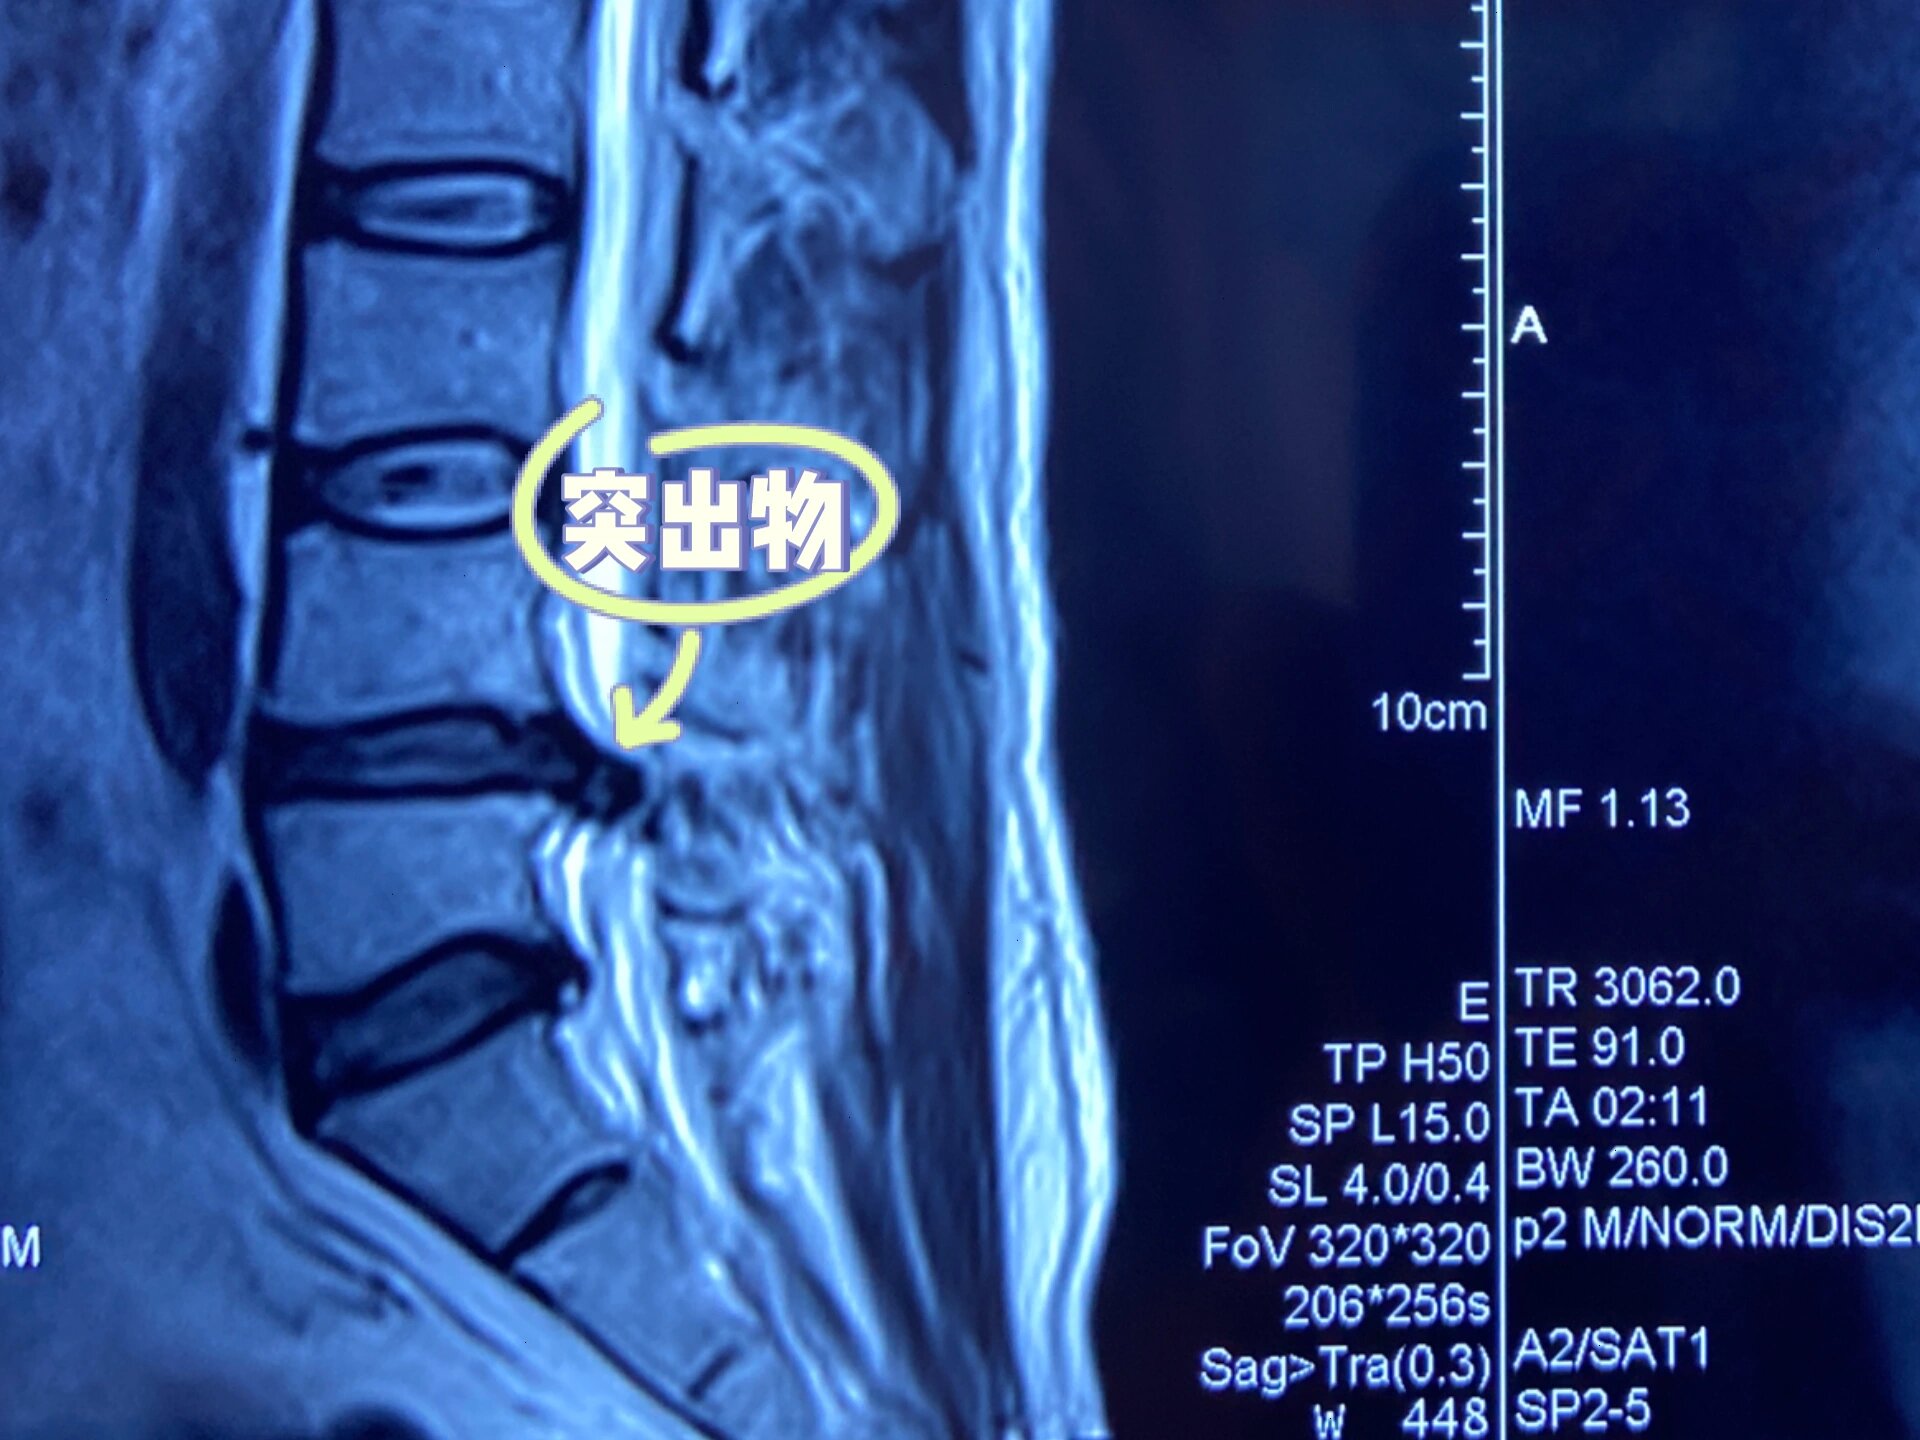

请问椎间盘变性是什么意思

椎间盘变性突出是指椎间盘发生变性改变后,髓核等结构突破正常边界向周围组织突出的病理状态一定义与病理机制椎间盘由软骨终板纤维环和髓核构成随着年龄增长慢性劳损等因素,椎间盘发生变性,表现为水分减少弹性下降,纤维环出现裂隙...